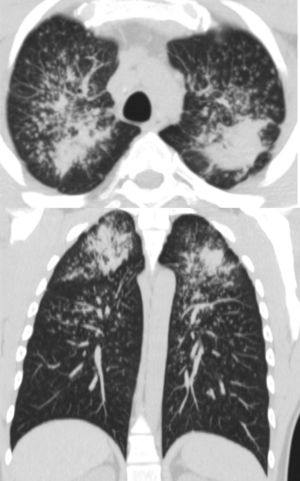

Chest HRCT is well known to increase sensitivity in the detection of progressive massive fibrosis (PMF).32 Nodular pattern findings, subpleural involvement and lymphadenopathies are similar to those of classic silicosis,33 although the presence of ground glass patterns of moderate extension in 30% of patients in our series should be noted, in addition to the existence of the usual nodules (Fig. 1). Several of the cases described by the Australian and Italian authors10,23 were significant for the presence of lymphocytosis in bronchoalveolar lavage, findings not described in classic silicosis. All this suggests a different form of the disease, probably more disseminated and aggressive than usual, which can develop more rapidly to an irreversible, fibrosing process. In our series, 10 patients met the criteria for accelerated silicosis.34 This group is too small to draw meaningful conclusions, but a profile is emerging of young people employed in cutting and polishing stone with increased use of conglomerates, who develop PMF (Fig. 2) and a tendency to lower lung function values. The histological and mineralogical study of samples obtained by transbronchial cryobiopsy35 helped exclude sarcoidosis in young people who showed a short latency period from the start of exposure (Fig. 3), and in other cases it revealed patterns of usual interstitial pneumonia associated with the deposit of silica particles (Fig. 4),36,37 which introduces therapeutic prospects not yet addressed in this disease.38